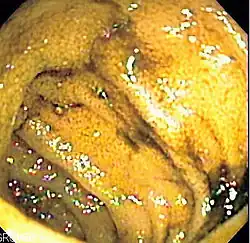

Enteroskopia dwubalonowa (enteroskopia "push and pull", ang. double-balloon enteroscopy, push-and-pull enteroscopy) – technika endoskopowa znajdująca zastosowanie przede wszystkim w badaniu jelita cienkiego. Została wprowadzona przez Hironori Yamamoto w 2001 roku[1]. Jest pierwszą diagnostyczną techniką stosowaną w gastroenterologii, która umożliwia uzyskanie obrazu całego przewodu pokarmowego w czasie rzeczywistym[2].

W tradycyjnej enteroskopii wprowadzenie aparatu do jelita cienkiego i dokładne obejrzenie wnętrza jelita cienkiego jest utrudnione lub uniemożliwione przez tworzące się pętle tego odcinka przewodu pokarmowego. Technika enteroskopii dwubalonowej polega na wprowadzeniu enteroskopu zakończonego balonem, i specjalnej tuby (overtube) wprowadzanej razem z enteroskopem w środku i później wycofywanej, również wyposażonej w balon[2]. Procedura wykonywana jest zazwyczaj w znieczuleniu ogólnym, chociaż niekiedy wystarcza sedacja[3]. Enteroskop jest wprowadzany w tubie przez jamę ustną i dalej, do jelita cienkiego, jak przy gastroskopii[1]. Następnie balon na końcu tuby jest wypełniany gazem, co stabilizuje aparat w dwunastnicy. Endoskop jest wprowadzany w kierunku dystalnym jelita na największą możliwą odległość, i wtedy napełniany jest balon na jego końcu. Balon na końcu tuby jest wtedy opróżniany a tuba zsuwana na koniec aparatu, i wtedy balon na jej końcu jest ponownie wypełniany. Cykl wprowadzenie endoskopu-przesunięcie tuby-cofnięcie endoskopu razem z tubą jest powtarzany dopóty, dopóki całe jelito cienkie nie zostanie obejrzane[4].